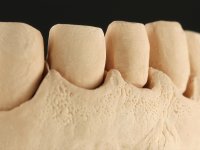

Realizado o diagnóstico e tomada a decisão quanto ao tratamento a executar, tornou-se importante definir qual a sequência de trabalho a adotar no sentido de conseguir a reabilitação da D.V.O. (V.D.O), de forma progressiva e equilibrada. Na primeira fase fez-se uma pré-impressão da arcada inferior com silicone tipo “putty” e em seguida realizou-se o preparo dentário de todo o sector posterior. O preparo para os overlays foi feito coronalmente à linha amelo cementaria no sentido de ser o mais conservador possível. A impressão foi feita com técnica de dupla mistura após afastamento gengival realizado com pasta de caulino. A provisória foi realizada com resina composta de polimerização dual. Em laboratório foram realizados os overlays após se ter aberto ligeiramente (1,5mm) a D.V.O. nos modelos montados em articulador semi-ajustável. Simultaneamente o sector antero-inferior foi encerado no sentido de acompanhar este aumento da D.V.O. Também foi confecionada uma chave de silicone translucido para posterior confeção dos provisórios antero-inferiores. Em boca foi primeiro realizada a provisionalização dos dentes anteriores utilizando resina composta previamente aquecida após preparação das superfícies dentárias para a adesão. Foi colocado o dique de borracha para promover o isolamento absoluto e posteriormente foram colados os overlays. Em laboratório foi realizada nova chave de silicone para confecionar os provisórios antero-superiores. Seguidamente em boca foram preparados os seis dentes antero-superiores após colocação do fio de afastamento gengival. Feita a preparação adequada das superfícies dentárias foi realizada a impressão com técnica de dupla mistura e a respetiva provisória. Em laboratório foram confecionadas 6 facetas feldespáticas num modelo de trabalho tipo “Geller”. A provisória foi removida e as facetas foram coladas em boca utilizando um isolamento relativo competente. Esta opção foi tomada em virtude de uma prévia experiencia negativa com a colocação do dique de borracha na mandibula. Após a colagem dos laminados antero-superiores foram dadas 12 semanas para avaliar a adaptação do paciente à nova situação e então iniciar a confeção das facetas antero-inferiores. Após colocação do fio de afastamento gengival. foram feitos os preparos dentários adequados e em seguida foi feita a impressão. Também foi feita a preparação do dente 3.4 que, entretanto, tinha sofrido uma fratura do overlay. As facetas e a restauração do 3.4 foram realizadas num modelo de trabalho tipo “Geller”. Após remoção da provisória, as facetas foram coladas em boca, utilizando um isolamento relativo pelas razões apontadas anteriormente. Após colocação do trabalho o paciente foi reabilitado por outros colegas com um implante na zona do 2.6 e substituição da coroa aparafusada sobre o implante colocado no local do 3.5. Posteriormente surgiram fraturas nos overlays dos dentes 4.7 e 3.7 que foram reabilitados com overlays em Zr.